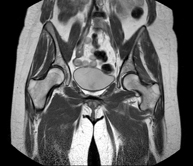

- Female pelvis MRI

This non-invasive diagnostic procedure uses an electromagnetic field and radio waves (from a transmitter and receiver) to acquire high-definition anatomical images of the pelvis. It is a radiation-free procedure. It is performed to study pathologies of the uterus, ovaries, fallopian tubes and vagina, whether they are of tumour, inflammatory or vascular origin. The procedure also enables the assessment of adjacent structures located in the pelvis, identifying any abnormalities. Sometimes intravenous contrast (gadolinium) is required to characterise the lesions.

- Male pelvis MRI

This non-invasive diagnostic procedure uses an electromagnetic field and radio waves (from a transmitter and receiver) to acquire high-definition anatomical images of the male pelvis. It is a radiation-free procedure. No prior preparation is required. In some cases, paramagnetic contrast (gadolinium) is required to characterise the lesions. This test enables the assessment of organs such as the urinary bladder, the junction between the ureters and the bladder, the prostate, the seminal vesicles, the urethra, the pelvic bones, etc.